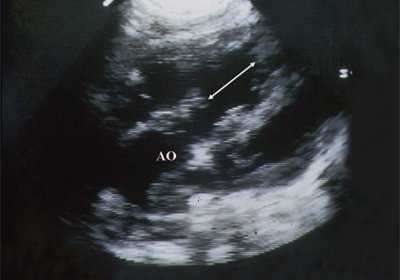

В равной степени это относится к дефекту межжелудочковой перегородки (рис. 6), простой форме транспозиции магистральных сосудов (рис. 7, 8), транспозиции магистральных сосудов с дефектом межжелудочковой перегородки (синдром Тауссиг - Бинга) (рис. 9), общему желудочку (рис. 10), общему артериальному стволу (рис. 10), двойному отхождению сосудов от одного из желудочков сердца (рис. 11).

Рис. 10. Общий желудочек с отхождением TRUNCUS ARTERIOSUS. Стрелками показано разделение TRUNCUS ARTERIOSUS на аорту и ствол легочной артерии.

Рис. 11. Двойное отхождение магистральных сосудов от левого желудочка. Длинная ось сердца. Магистральные сосуды инвертированы и отходят от левого желудочка. Аорта расположена "верхом" над дефектом межжелудочковой перегородки (стрелка).

LV и RV - левый и правый желудочек, АР - легочная артерия, АО - аорта, VSD - дефект межжелудочковой перегородки.